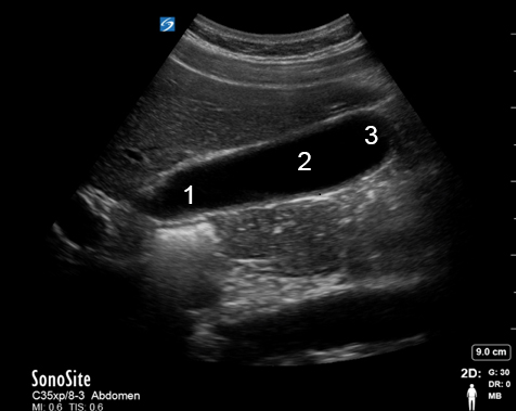

Gallbladder 1 Image

Neck

Body

Fundus